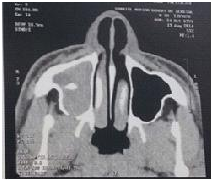

The lesion extended to nasal cavity, involving the medium turbinate obliterating the ostiomeatal complex. Left nasal cavity and sinus showed no alterations (Figure 1&2). Tomography conclusion suggested chronic sinusopathy caused by fungus or polyps. Transnasal endoscopic surgery combined with Cadwell Luc approach was performed based on the tomography images. The lesion was easily avulsed from adjacent tissue and removed completely. It was sent to anatomophatological analysis. Gross examination of the specimen revealed a friable, reddish brown coloured single lesion with elastic density. The microscopic examination disclosed squamous mucosa with chronic inflammation, an endothelial cell proliferation with papillary formations and areas of haemorrhage and neovascularization (Figure 3). There was no complication on postoperative course. The patient had no recurrence of the symptoms after 12months past the surgery.

Figure 2 Axial TC of the paranasal sinuses showing maxillary opacification with extension to nasal cavity, involving the medium turbinate.